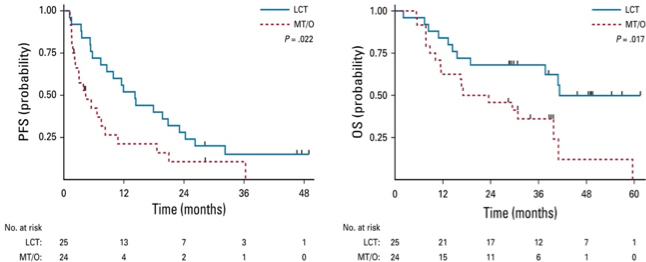

外科手术是早期NSCLC(I期和II期)最主要的治疗手段,部分IIIA期NSCLC也是我们外科医生的治疗对象。传统观念认为,一旦临床诊断为IV期,外科的治疗价值就非常有限,绝大多数仅仅是活检协助诊断。近年来,随着理念的不断更新,越来越多的证据显示,外科手术在晚期NSCLC的治疗仍然有重要作用。2016年Gomez等人在Lancet Oncology杂志上报道了针对肺癌寡转移患者开展的一项随机对照研究,发现对于全身治疗有效的基础上加上局部治疗(包括手术和放疗等),比维持治疗可以显著提高无疾病进展时间(11.9 v.s.3.9 m, P=0.005),而且并没有增加3级以上不良反应的比例 (Gomez DR, Blumenschein GR, Jr., Lee JJ, et al. The Lancet Oncology. 2016;17:1672-1682.)。今年在Journal of Clinical Oncology(JCO)杂志,Gomez 等人进一步报道了更新的随访数据,发现全身治疗有效的基础上加上局部治疗,比维持治疗还可以显著提高整体生存期 (41.2 v.s. 17.0 m, P=0.017) (Gomez DR, Tang C,Zhang J, et al. Journal of Clinical Oncology. 2019;37:1558-1565.)。需要指出的是,这项研究入组的都是全身接受化疗或靶向治疗的患者。当前进入免疫治疗时代,对于驱动基因阴性晚期NSCLC患者,无论ORR、PFS 或者OS,免疫治疗都显示了更好的治疗效果。因此,可以预见,未来会有越来越多的晚期NSCLC寡转移患者,全身免疫治疗后可显示更好的疾病稳定,从而有机会接受手术治疗作为局部控制。当然,对于身体不能耐受手术的患者还有机会接受其他局部治疗,如放疗或消融治疗等。

图1. 相比维持治疗(MT/O),全身治疗有效的基础上增加局部治疗(LCT)可以提高无疾病进展时间和整体生存期(GomezDR, Tang C, Zhang J, et al. JCO. 2019;37:1558-1565.)